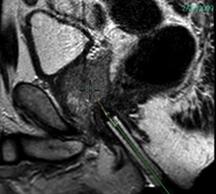

Fig. 1 Diffusion-weighted MRI image of the prostate gland.

MRI has a role in imaging and analysis of DCE prostate images as well as interventional planning, and is a way to further evaluate men with prostate cancer. Staging, node detection and evaluation of metastatic disease are areas where MRI has an evolving and important place4. Detection, localization and subsequent biopsy are possible in even outpatient environments (Fig. 1, Fig.2)5.